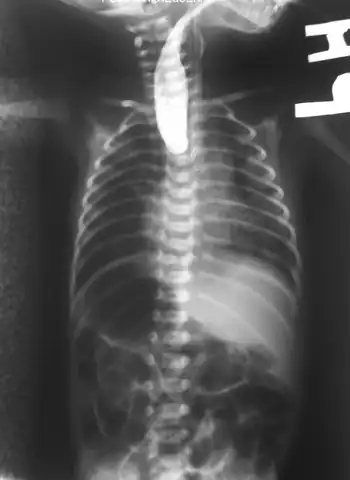

On plain X-ray, a feeding tube will not be seen pass through the esophagus and remain coiled in the upper oesophageal pouch.[8]

Plain X-ray of the chest and abdomen showing a feeding tube unable to move beyond an upper esophageal pouch. -

Plain x-ray with contrast in the upper esophagus above the atresia.